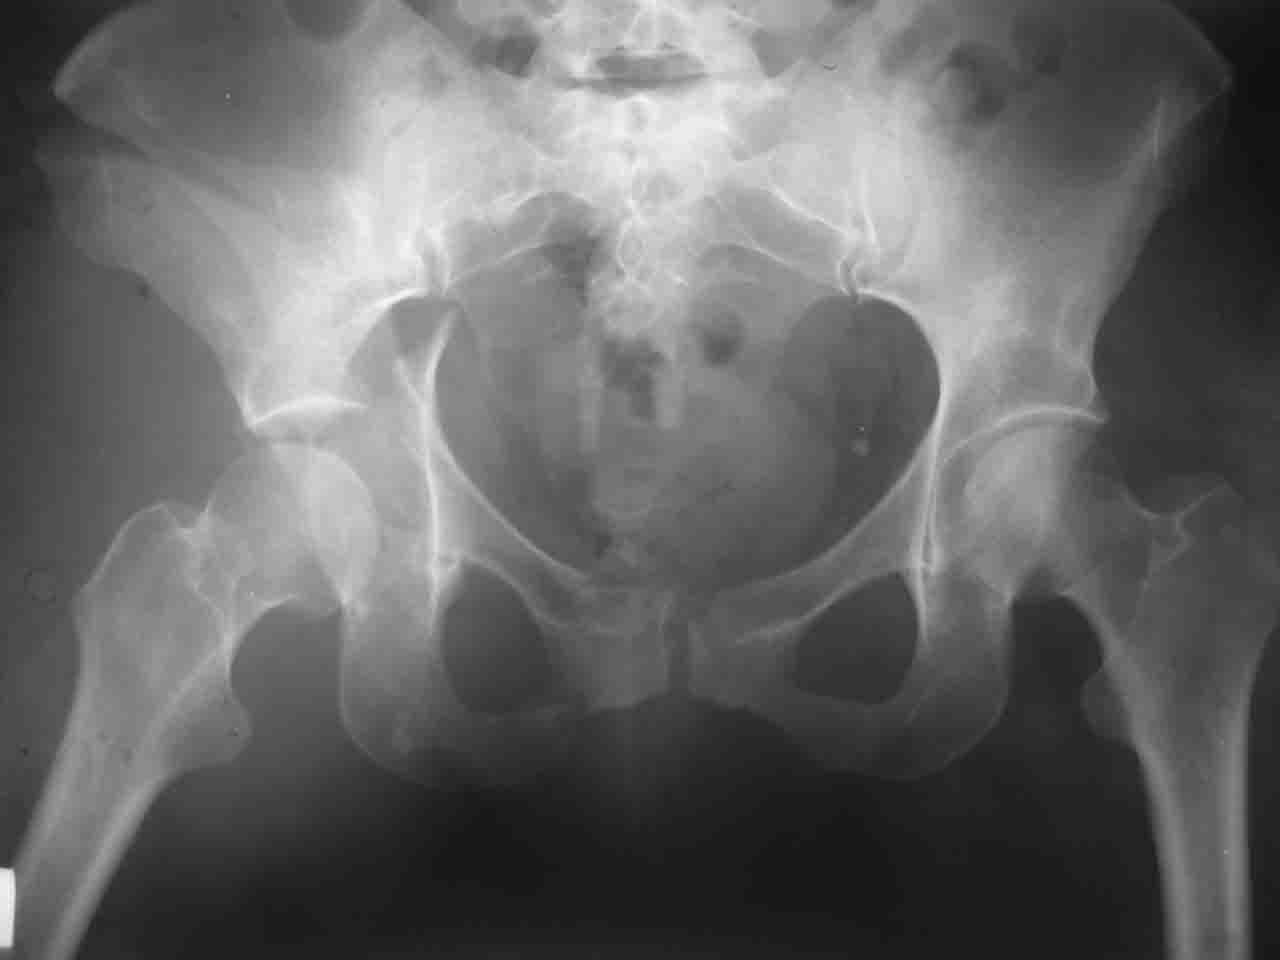

Re: Перелом вертлужной впадины

Спасибо за комментарии и рекомендации. Откровенно говоря, больного я прооперировал на прошлой неделе, через 5 дней после аварии и проблем с ним пока никаких нет, на удивление при достаточно обширной диссекции (илиофеморальный доступ) болей практически нет, так что больной самостоятельно садится в кровати, выполняет активные движения в оперированном суставе, сгибая до 60 градусов пока, далее с ассистенцией.

Причиной обращения к сообществу были возникшие непосредственно после операции сомнения и разочарования полученным качеством репозиции: а надо ли было трогать перелом вообще, репозиция передней колонны технически была очень сложна для меня, хотя реконструкции была в той же последовательности, что Д-р А.В.Рунков рекомендовал, в какой-то момент безуспешных манипуляций стал думать о *вторичной конгруэнтности*, которую не так давно обсуждали на

форуме и скелетном вытяжении. С репозицией и фиксацией задней колонны и отдельно задне-верхней стенки впадины проблем не возникло. Послеоп. Рг граммы в приложении. Если возникнут какие-либо дополнения или поправки - был бы признателен.